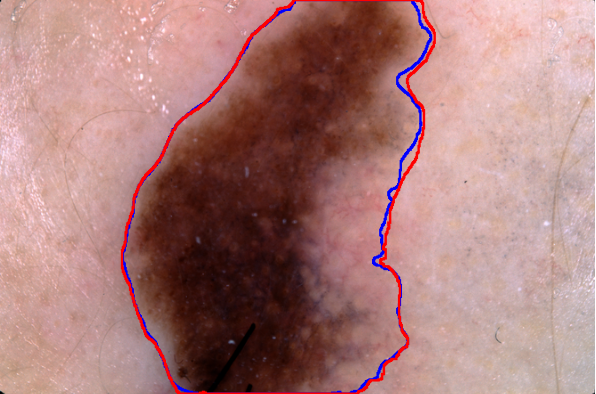

Compare the quality of the two segmentation masks. The fast mask is in blue and the slow mask is in red:

HighlightImage[img, {"Boundary", Blue, Image[fastMask], Red, Image[slowMask]}]